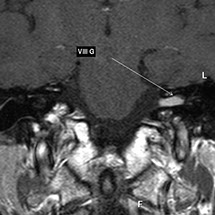

L'imagerie par résonance magnétique (IRM) est une technique qui permet d'obtenir des images dans n'importe quel plan de l'espace.

L'IRM permet de différencier les différents types de tissus mous. C'est ce qu'on résume en disant que l'IRM a une excellente sensibilité de contraste.

Pour se convaincre de la sensibilité de contraste de l'IRM, il suffit de comparer des coupes de scanner et d'IRM du cerveau, du rachis (colonne vertébrale) et des muscles et d'observer les détails anatomiques et topographiques produits par ces deux techniques.

> A l’étage cérébral, l'IRM est l'examen de routine dans la recherche d'un accident vasculaire, d'une tumeur ou d'une sclérose en plaques. L'IRM est de loin supérieure au scanner dans la recherche des lésions du parenchyme cérébral, mais aussi de l’hypophyse et des orbites. L'IRM permet également d'étudier les artères du cou et du cerveau.